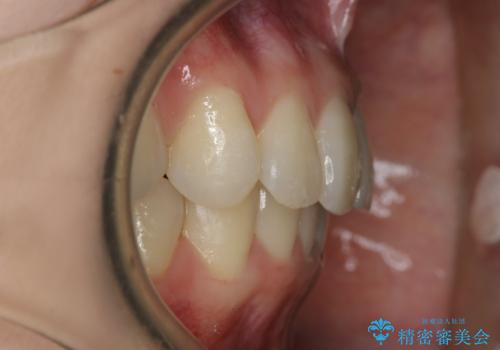

一見そこまで大きなガタつきはないようにも見えますが、前歯の角度の不揃いや噛み合わせのズレなどから見え方に影響が出てしまっていました。

抜歯は全く必要のないレベルのガタつきだったため、マイクロインプラントを用いて歯全体を後方に移動させていくことできれいな歯並びを獲得することができました。

マウスピースとマイクロインプラントを組み合わせることで、抜歯をしなくても歯並びを治すためのスペースを作ることができます。奥歯から順に移動させていくので前歯に変化が出るまでには時間がかかりますが、どの分健康な歯を抜歯することなく理想的な歯並びを手に入れることができます。